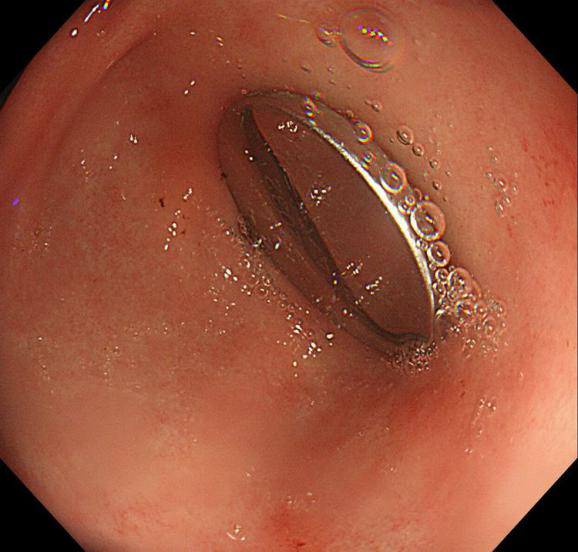

邵阳3岁宝宝误吞纽扣电池 在胃内停留1天半送长沙抢救

图片尺寸578x552